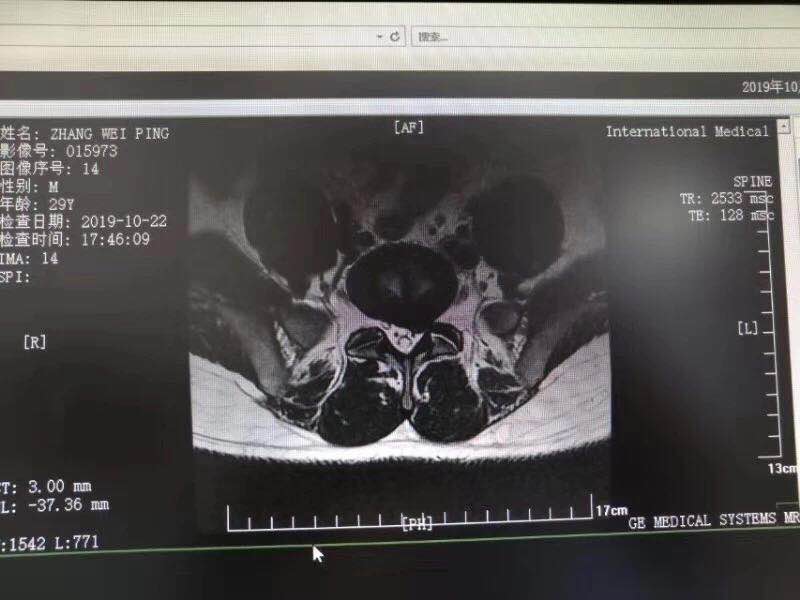

10月28日,西安國際醫(yī)學(xué)中心骨科醫(yī)院脊柱外科成功完成首臺椎間孔鏡手術(shù)。該手術(shù)結(jié)合加速康復(fù)外科(ERAS)理念的精細化管理和臨床路徑管理,采用微創(chuàng)的孔鏡技術(shù),為解除患者病痛。術(shù)后,患者左下肢放射痛即刻消失,第二天便下床活動鍛煉,已……